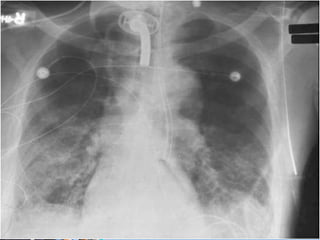

• Diagnosis is imprecise and usually

based on a Combination of:

– CXR factors - new or changing infiltrates

• VAP isa Nosocomial Pneumonia = Hospital acquired • Diagnosis is imprecise and usually based on a Combination of: – Clinical factors - fever or hypothermia; change in secretions; cough; apnea/bradycardia; tachypnea – Microbiological factors - positive cultures of blood/sputum/tracheal aspirate/pleural fluids – CXR factors - new or changing infiltrates